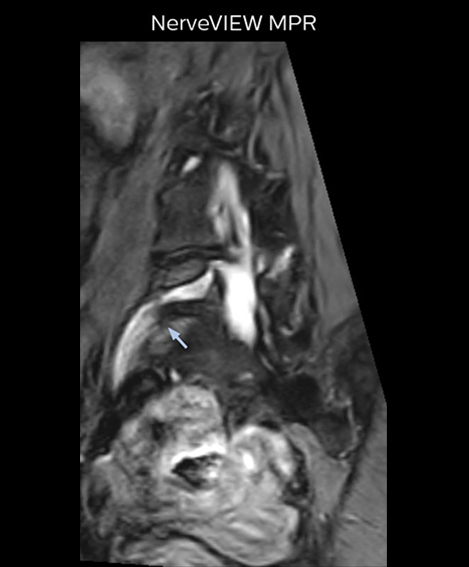

“Recently, the two surgical methods extreme and oblique lateral interbody fusion (XLIF and OLIF) have become mainstream for minimally invasive treatment of lumbar spinal canal stenosis and intervertebral foramen stenosis. With these surgical techniques, the spine is approached from the flank, and prior knowledge of the exact anatomy of the lumbosacral plexus would be extremely helpful. To that end, high slice resolution (less than 1 mm acquisition) that enables sharper sagittal MPR images will be needed.”

“For both brachial and lumbar plexus, we are currently using a 230 mm FOV and voxels of about 1 x 1 x 2 mm acquired (1 x 1 x 1 mm reconstructed). This provides us a good representation of the nerves, even though this FOV is relatively small. Regarding the inplane resolution, we hope to be able to bring that down to 0.7 mm, similar to our typical 2D multislice T2W images,” says Tanji.

Implementing NerveVIEW without lengthening exam time “The source images of NerveVIEW exhibit a contrast similar to STIR or fat-suppressed T2-weighted images. So, in our neurography exams we are replacing the 2D T2-weighted coronal sequence with 3D NerveVIEW. With this, we add a lot of useful information without adding scan time. This is important for patients with severe lower extremity symptoms, as they often find it difficult to maintain still during the whole MRI examination, so the exam should be as short as possible.” “We have currently implemented 3D NerveVIEW on our Achieva 3.0T dStream MRI system only. Because the 3D NerveVIEW method is based on a background signal suppression technique, we decided to use the high SNR of our 3.0T MRI system for obtaining the best possible visualization of peripheral nerves,” says Tanji. “Where NerveVIEW of the lumbar plexus is currently used as a subroutine scan for patients with strong lower limb symptoms, its use for visualization of the brachial plexus, is currently limited to special cases such as schwannomas and neuritis, usually only 1 or 2 cases per month.”